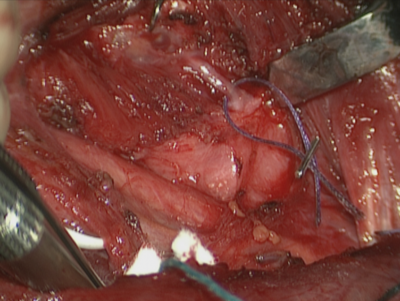

In unilateral vocal fold paralysis (UVFP) the goals of treatment are to improve voice, reduce aspiration and facilitate a more effective cough. The rehabilitative approach depends on the requirements of the patient, the fitness for surgery and likely best outcome. Non-selective reinnervation is a technique that aims to restore muscle tone and bulk to the paralysed hemilarynx, although movement coordinate with respiration and phonation is not achieved. The technique involves the anastomosis of a branch of the ansa cervicalis to the distal stump of the recurrent laryngeal nerve (Figure 1). It is an alternative to medialisation thyroplasty (+/- arytenoid adduction) where an implant is used to push the flaccid vocal fold into a more favourable position to facilitate glottic closure.

Figure 1. Identification of the RLN as it enters the larynx. A skin hook is used to rotate the larynx and fibres

of the inferior constrictor are dissected off the posterior border of the thyroid cartilage to expose the nerve.